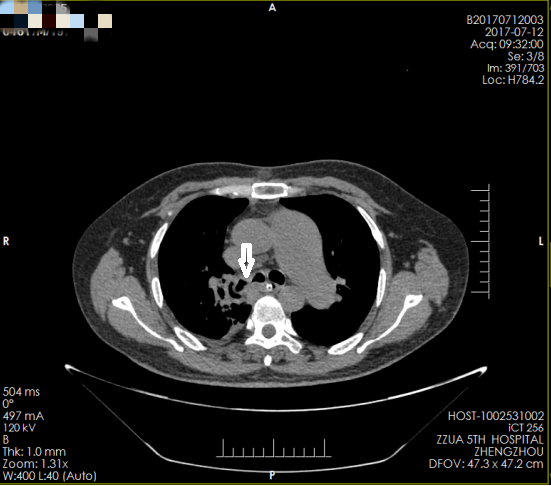

正所谓天无绝人之路,通过亲戚朋友介绍,霍先生的妻子打听到郑州大学五附院心胸外科对处理危重胸外伤有丰富的经验,便抱着试一试的态度连夜转到郑州大学五附院。住院后在高兴才主任指导下,患者的病情一度得到控制,入院后的一周后患者多次突然出现胸闷、气促、呼吸困难,心电监护示:心率110次/分,氧饱和60%左右。值班医师陈涛马上安排急诊床旁胸片检查,结果显示:右肺未见肺纹理(图一),出现了临床上可怕的“大白肺”,在与冯光强副主任医师商议后,考虑患者痰栓阻塞气管引起右肺实变,病情危重。与患者家属沟通后,把霍先生转入呼吸重症监护室,予以气管插管,同时呼吸机辅助正压通气,待情况稳定后行气管镜发现,右主支气管狭窄,气管镜不能通过。复查胸部CT(图二)也证实了气管狭窄的存在。

▲ 图二(箭头所示为气管狭窄)